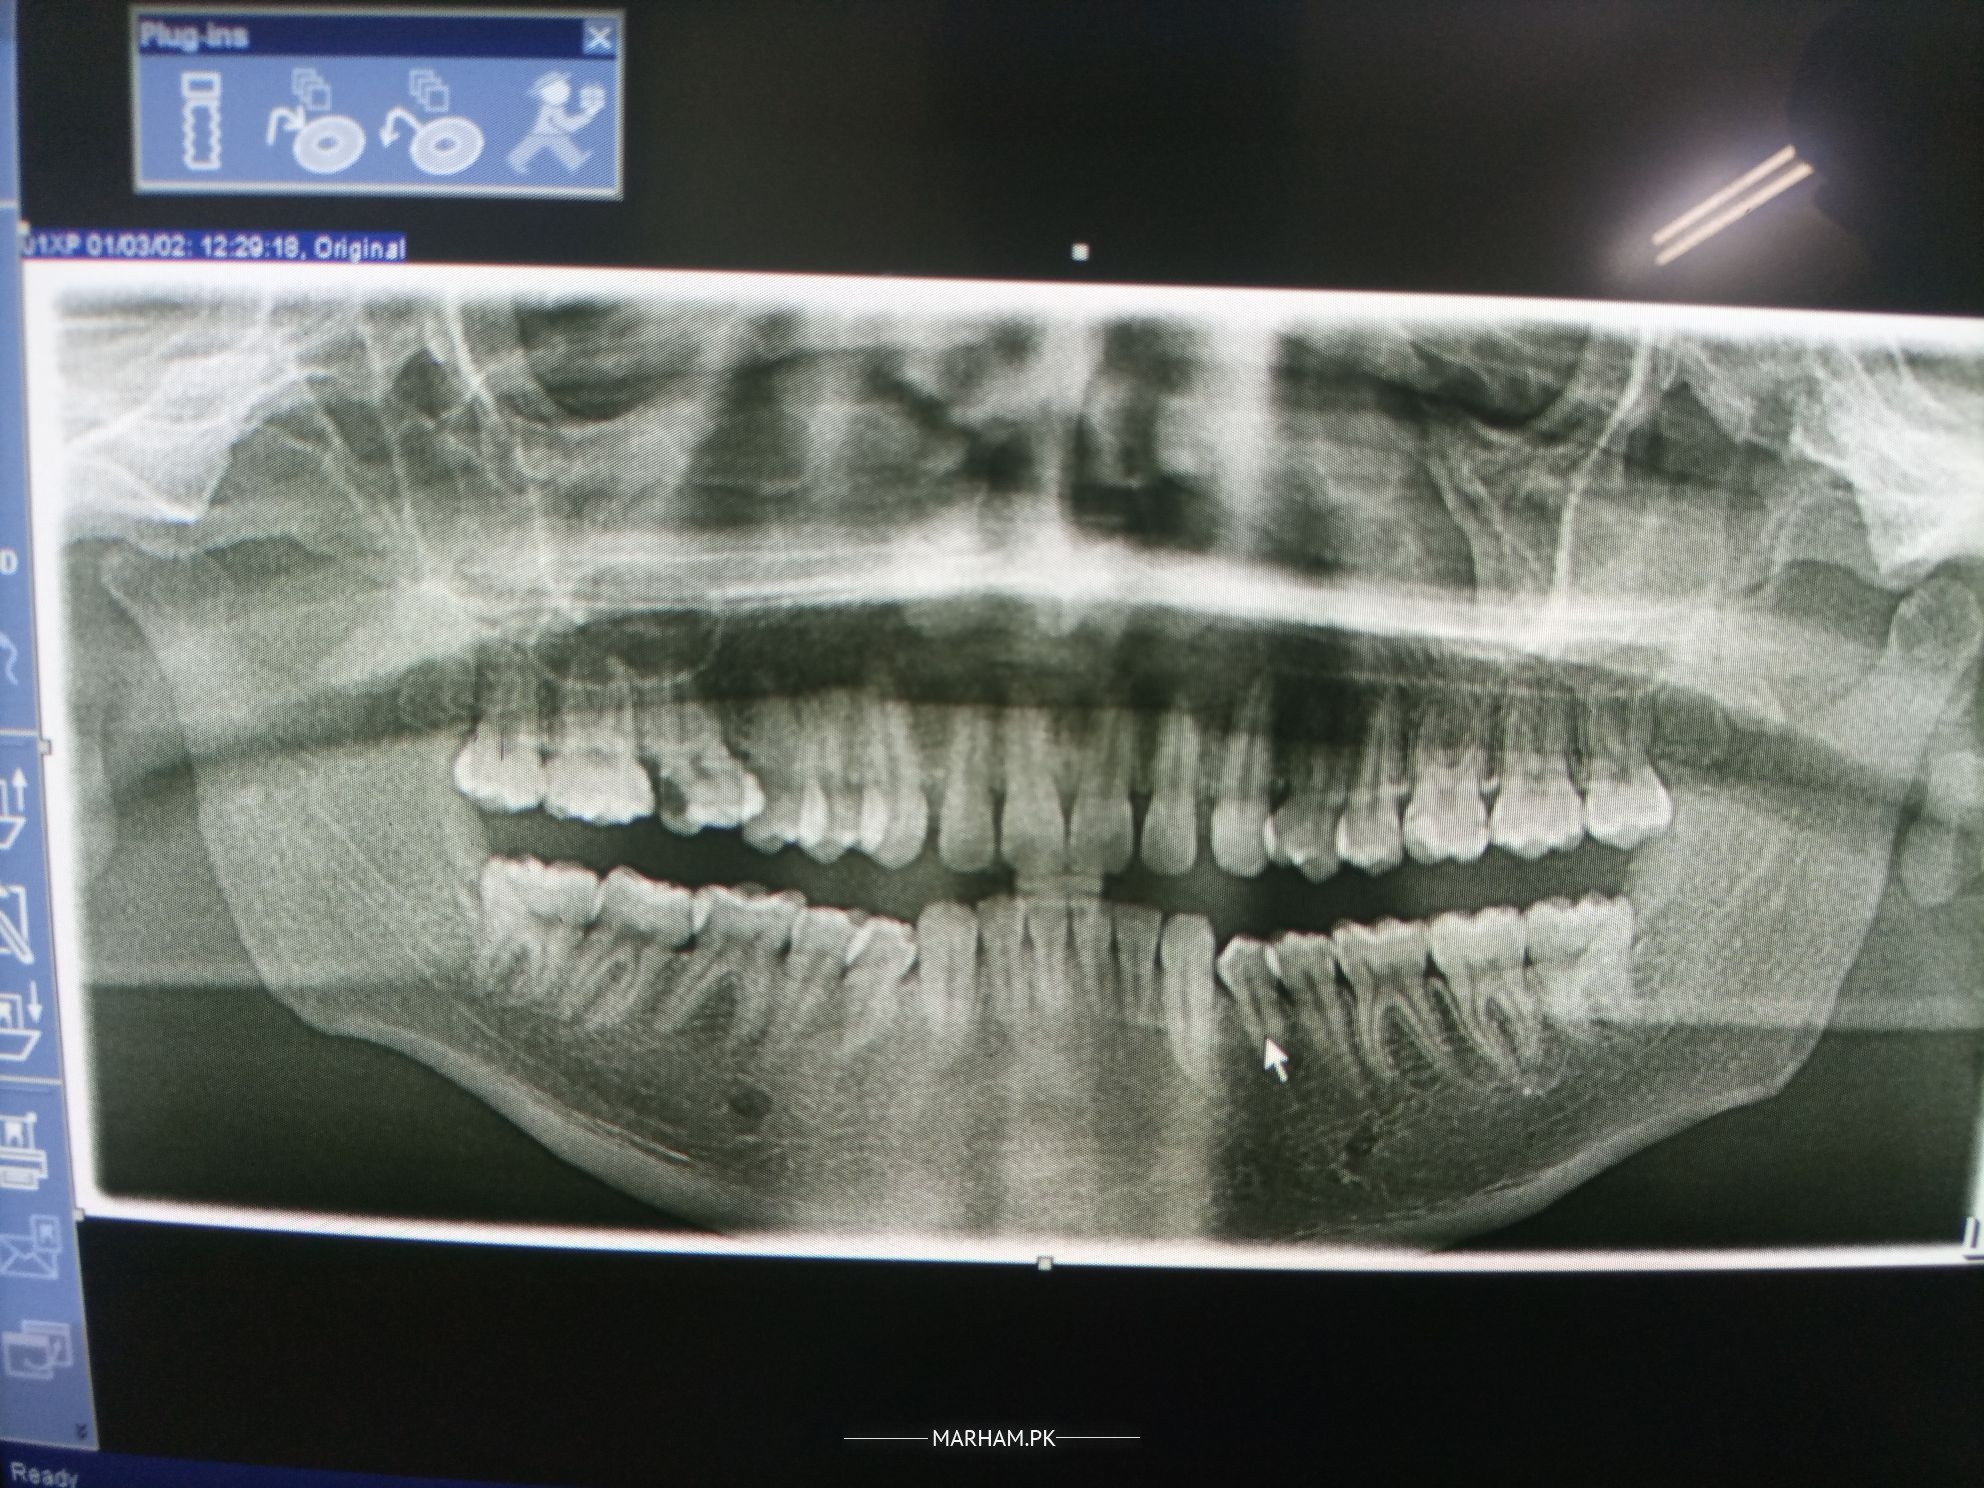

Can you suggest me the treatment from these x- rays image of my teeths.

With the little information you have provided, I suggest treatment for your upper right first molar; secondly, a clinical evaluation is necessary for further comments on the case.

as per the x-ray. two of the upper right side teeth are damaged. including molar tooth,which needs RCT and crown and two premolars on the lower left side. which requires filling treatment

also get professional teeth cleaning done and revisit dentist as adviced